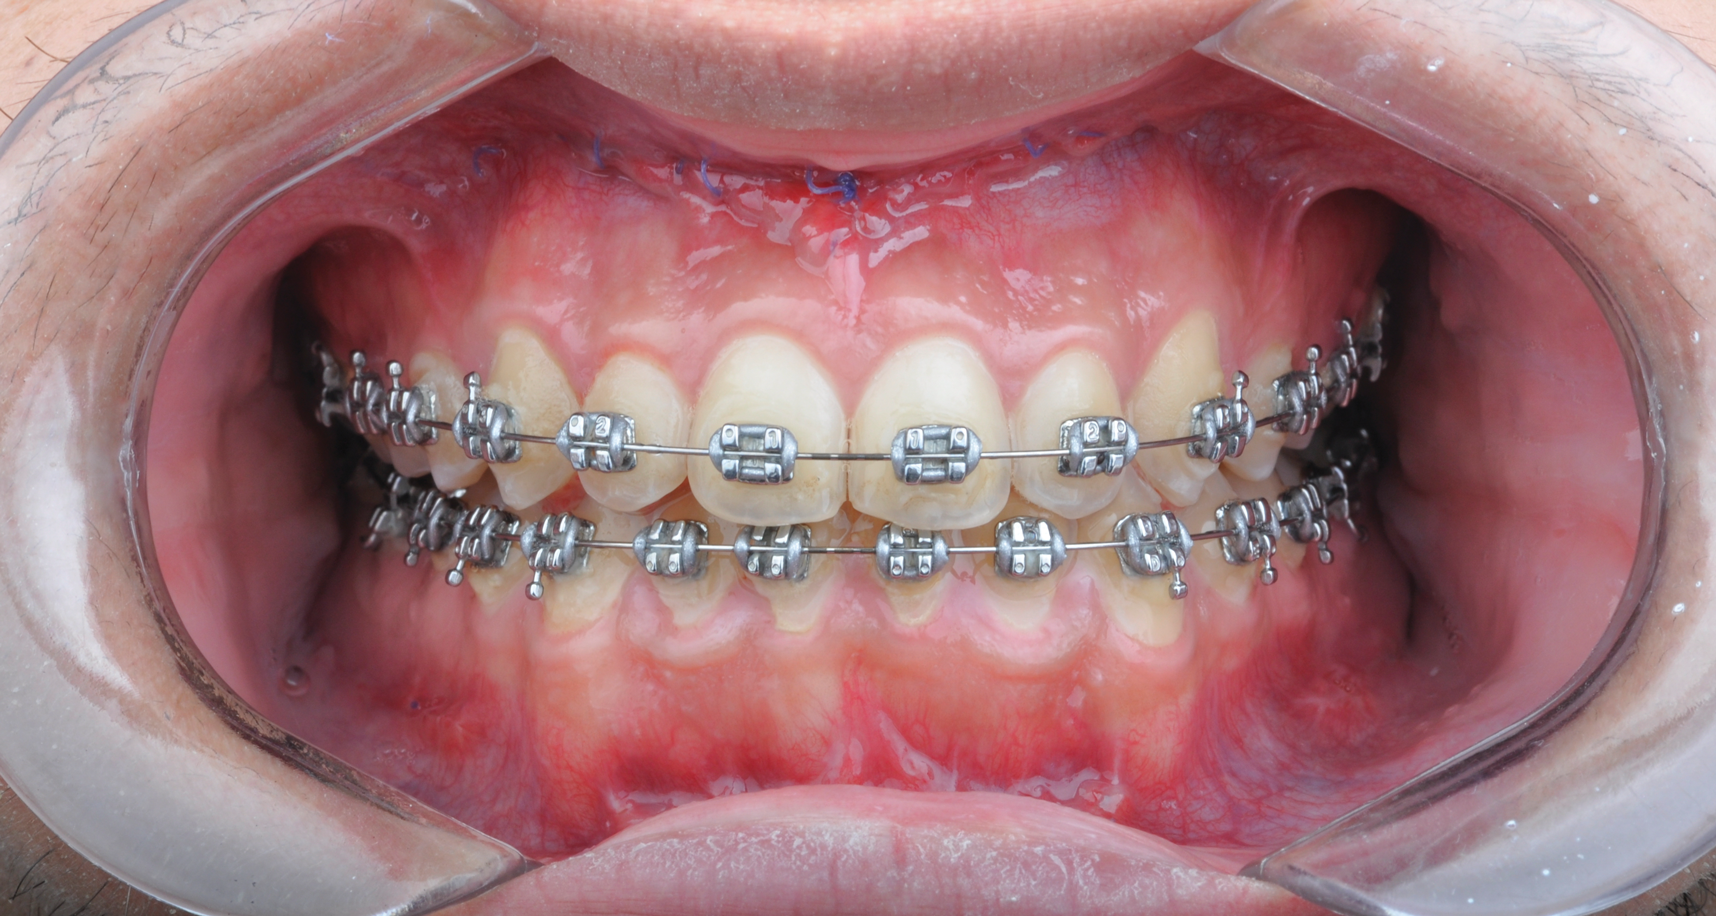

Fig 10. Postsurgical orthodontics for bite settling after the surgical procedure. Surgery for this patient consisted of maxillary surgical advancement, mandibular surgical asymmetric setback, and genioplasty (chin correction). Note the anterior and posterior crossbite was corrected and a class I occlusion was obtained.

Figure 10